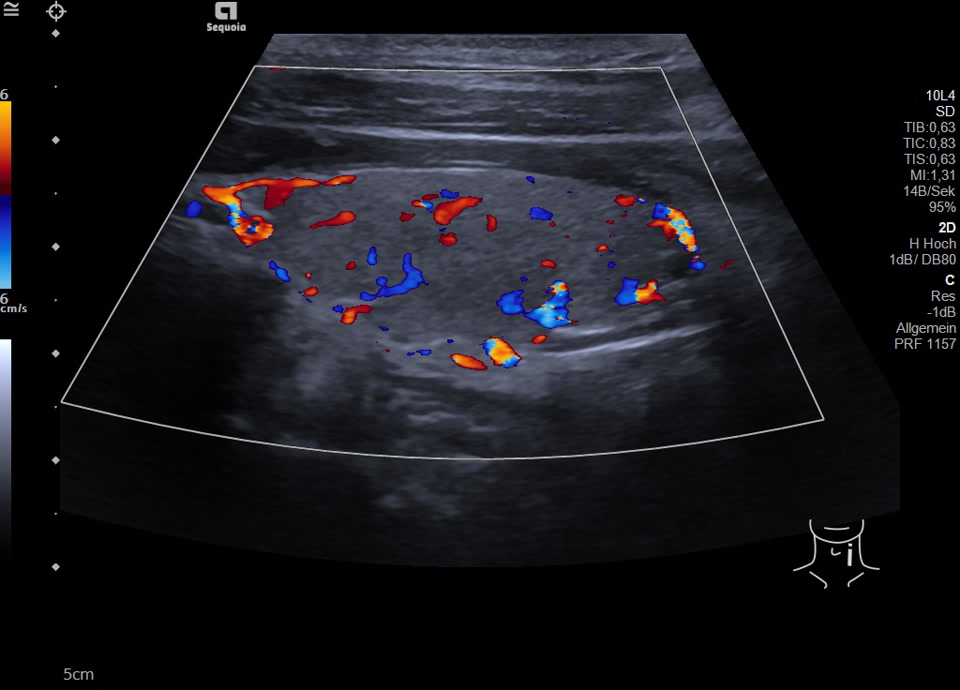

36-jähriger Patient mit Tremor, Tachykardie, Exophthalmus und Gewichtsverlust. Sonographisch stellt sich die Schilddrüse beidseits mit echoarmer inhomogener Parenchymstruktur dar. Gesamtvolumen 20,5 ml. Farbdopplersonographisch hypervaskularisiert. Laborbefunde: basales TSH erniedrigt, T3/fT4 erhöht, TRAK positiv. Befundkonstellation vereinbar mit M. Basedow. Unter Therapie mit Thiamazol und Propranolol beschwerdefrei. Bei Verlaufskontrolle zwei Jahre später sonographisch echoreiches minimal inhomogenes Parenchym bei normalem Volumen (15 ml).